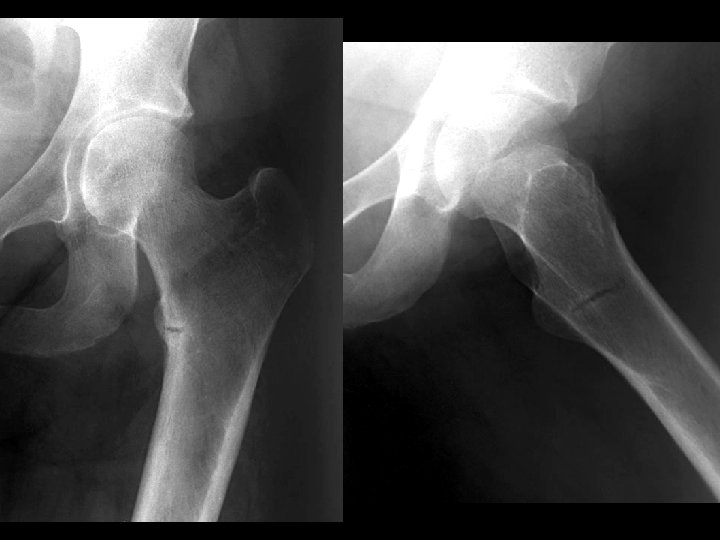

Bilateral SCFE • • Findings: – posteromedial displacement of femoral epiphyses Most common cause of limp in adolescents SH-I shearing fx high incidence in black, overweight pubertal males 75% uni, 25% bi Look for line along lateral femoral neck to transect 1/6 th of epiphysis Must be pinned or fixed